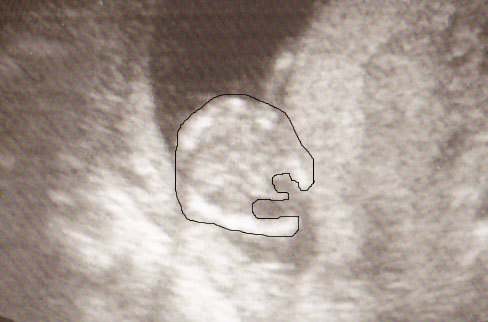

Результаты: УЗИ, КТГ, доплера, скринингаЯ так поняла, что на этом фото ребеночек как будто на попке сидит. Вид снизу. Посмотрите, может у кого было похожее фото, мальчик это или девочка?По правой стороне это у меня тонус, а попка слева внизу.Может у кого есть похожее фото?

Вот увеличила и обвела

срок 13,5-14 недель, узист сказала что мальчик)В 11 недель тоже предположили что мальчик.

Просто может были у кого такие снимки, интересно знать,что из этого вышло.